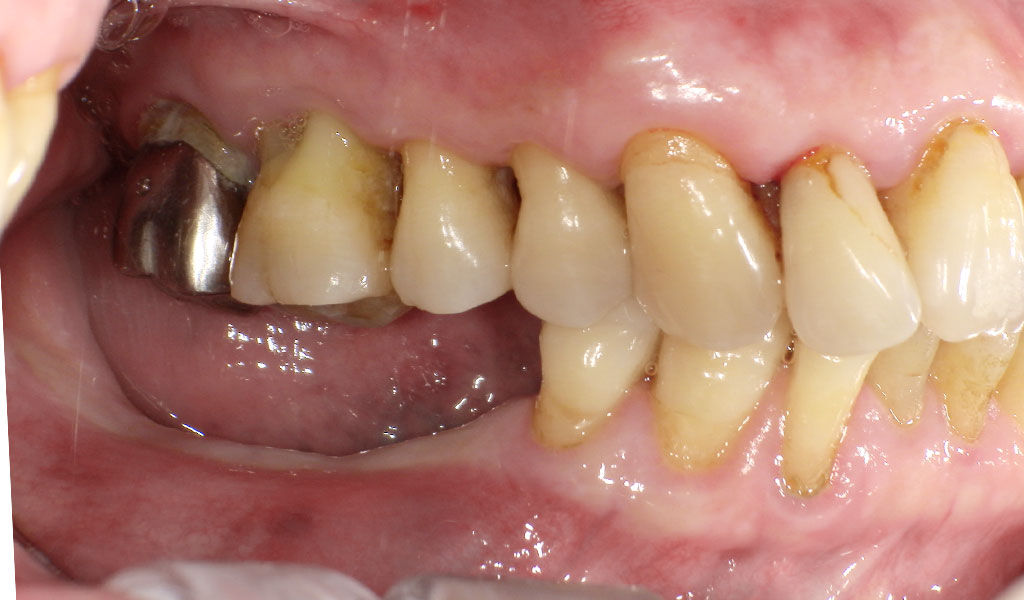

Before(左下6,7番、右下5,6,7番)

Before(左上6番、下6,7番)

Before(右下5,6,7番)